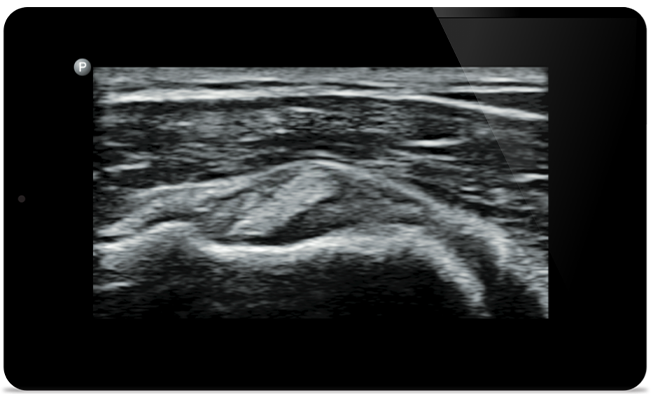

Use Lumify handheld ultrasound for musculoskeletal to detect soft tissue injuries with high-definition imaging of muscles, joints, ligaments, tendons and cartilage.

Lumify helps you see the fine details in muscles, joints, ligaments, tendons and cartilage to make a more accurate diagnosis of injuries.

Lumify can help you assess patients from head to toe, whether it’s plantar fasciitis, tendonitis or bursitis in the patellar tendon, or even shoulder instability in the rotator cuff.

SonoCT reinforces real tissue imaging while eliminating random artifacts. This technology produces images superior to conventional imaging in up to 94% of patients.

Get the full picture with clear whole-body imagery for a fast, accurate response during MSK examinations.